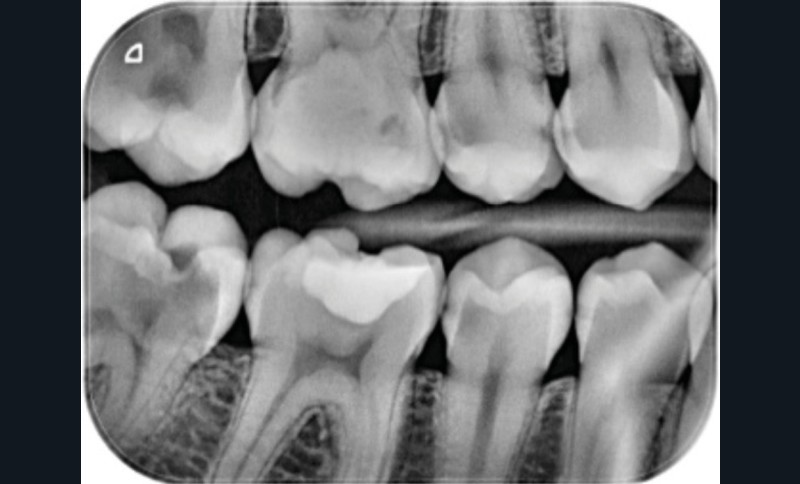

À l’examen dentaire, des lésions carieuses cavitaires de type ICDAS 5 (cavité franche avec dentine exposée sur moins de la moitié de la surface occlusale) sont visibles sur 37, 47, 27 et 26 (fig. 1) [2]. Une lésion ICDAS 4 (changement de teinte de la dentine visible à travers l’émail apparemment intact ou présentant des signes de rupture localisée) est visible sur 17. Des lésions ICDAS 2 (déminéralisation de la totalité de l’émail visible sur surfaces non séchées) sont mises en évidence au niveau des zones cervicales vestibulaires de 35 et 36.